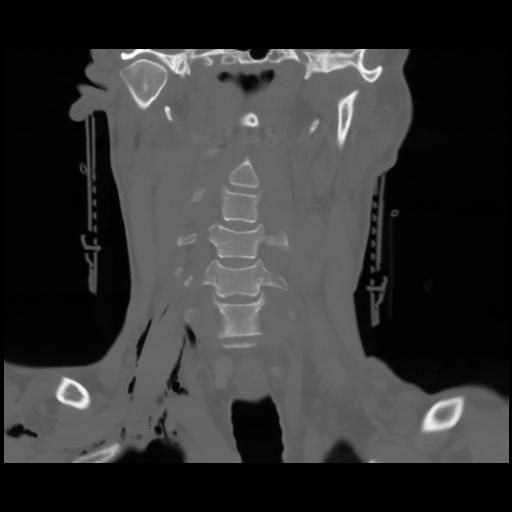

13 P.BLANDAS,,Coronal,2.000,P.BLANDAS,Coronal,